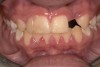

A 9-year-old girl, referred to a prosthodontic office by her pediatric dentist, presented with her mother’s chief complaint: “The kids are teasing her about her big front tooth.” Findings from radiographic and clinical examinations revealed fused maxillary central-peg lateral incisors, teeth Nos. 7 and 8, and a congenitally missing lateral incisor, tooth No. 10 (Figure 1 through Figure 3). An implant was selected as the ideal treatment to replace tooth No. 10 when somatic growth was complete. A diagnostic wax-up was fabricated to determine if the fused tooth could be made to resemble two teeth, using pink composite to give the illusion of an interproximal papilla. The patient was referred for an orthodontic consultation to plan for closure of the diastema between teeth Nos. 8 and 9 and achievement of proper alignment for implant No. 10. The patient was also referred to a periodontist for pretreatment assessment of the tooth No. 10 site. An endodontist was consulted should exposure of the large pulp occur during tooth preparation.

Fig 1 and Fig 2. Pretreatment photographs. Patient at 9 years of age on presentation.